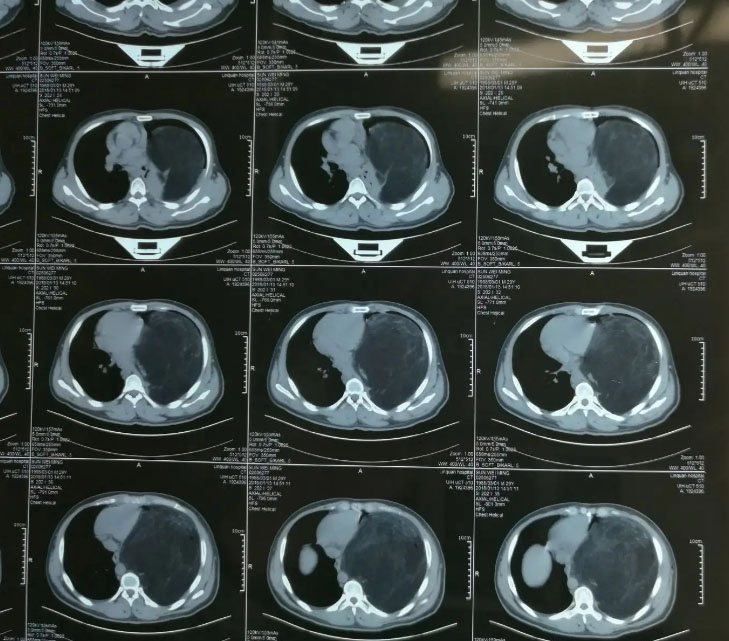

The Department of Thoracic Oncology is characterized by lung cancer, malignant thymoma, pleural mesothelioma and so on, with rich clinical experience, advanced treatment concept and standardized individual diagnosis and treatment. The department tracks the latest international research progress, combined with decades of clinical experience, to create a standardized and reasonable comprehensive treatment program for patients, and is good at internal medicine and comprehensive treatment of various types of lung cancer (chemotherapy, targeted drug therapy). Standardized cancer pain management and palliative treatment, while carrying out tracheoscopy for the diagnosis and treatment of lung masses. We conduct multi-disciplinary consultation with thoracic surgery, radiotherapy, interventional department, traditional Chinese medicine, imaging department, pathology department and nuclear medicine department to provide patients with the most authoritative, convenient and reasonable comprehensive diagnosis and treatment arrangement.